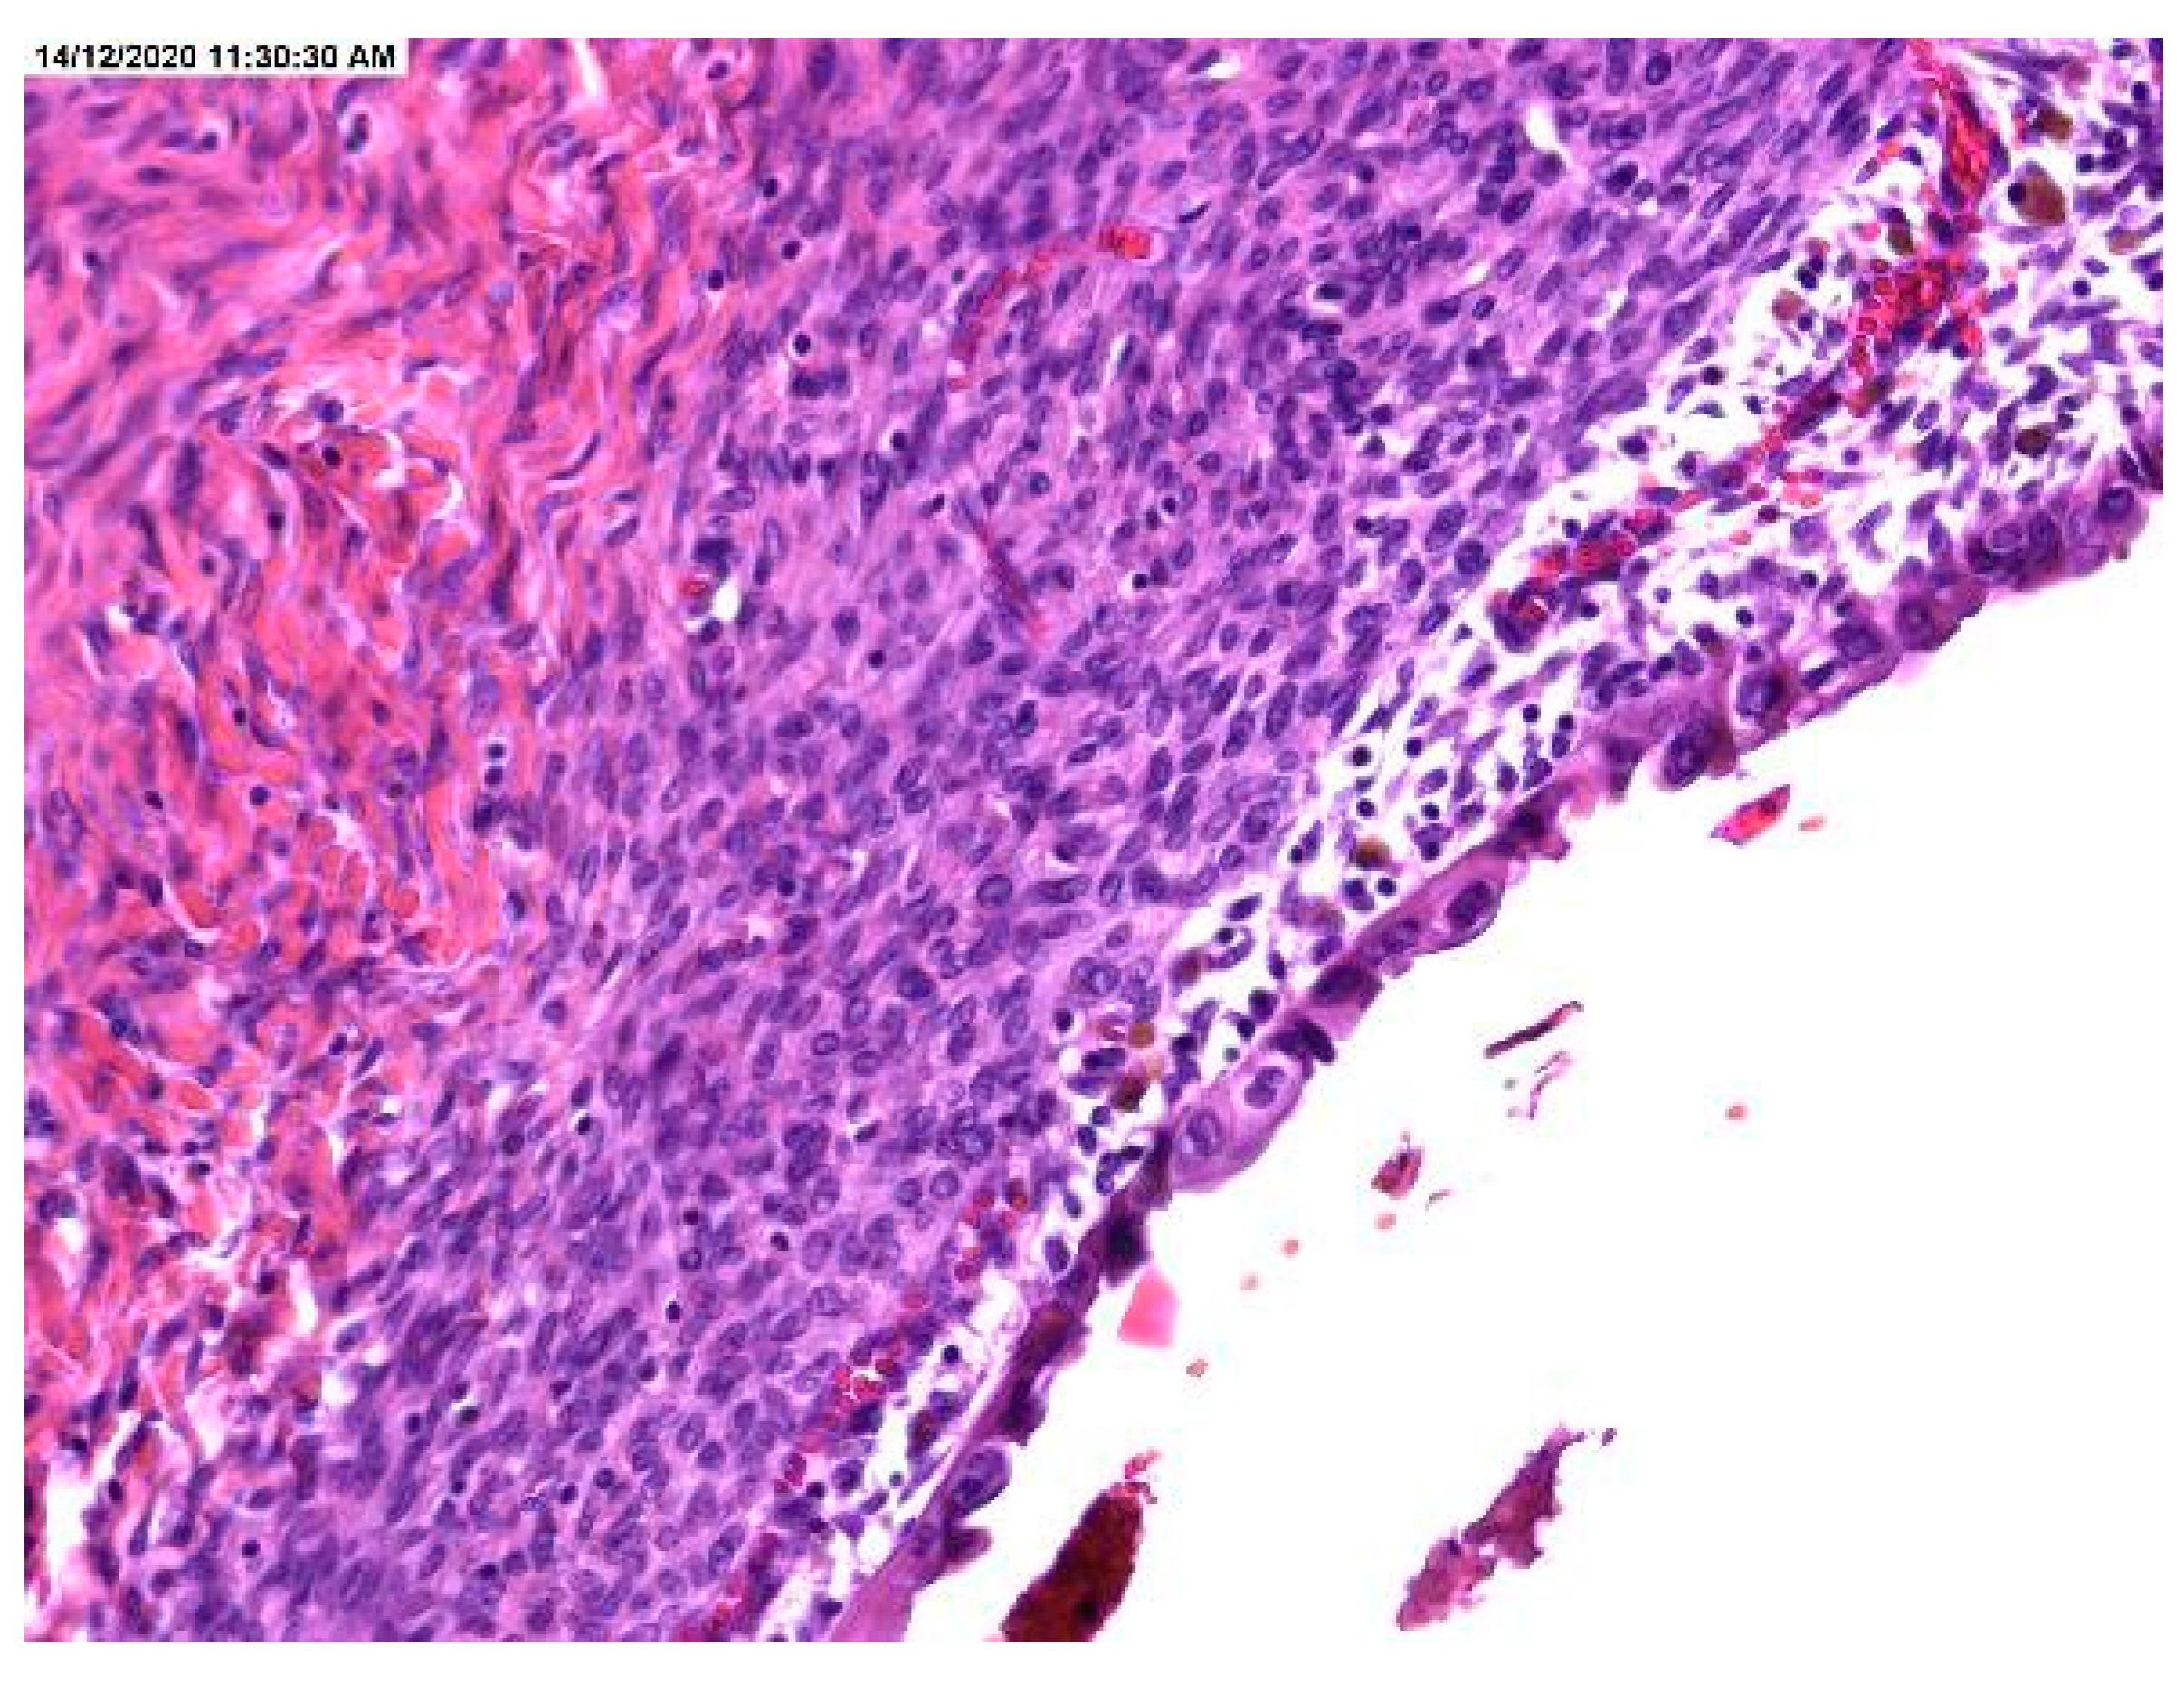

Chocolate Cyst Pathology Ovarian endometriotic cysts (endometriomas) have fibrotic walls, a smooth lining and dark brown cyst contents (chocolate. pathology is an educational resource with high quality pathology images of benign and malignant neoplasms and related entities. This is a section through an enlarnged 12 cm ovary to demonstrate a cystic cavity filled with old blood typical for. Ovarian endometriotic cysts (endometriomas) have fibrotic walls, a smooth lining and dark brown cyst contents (chocolate. An ovarian endometrioma is a cyst that’s filled with the same fluid that’s in the lining of your uterus (endometrium). These lesions are commonly referred to as chocolate cysts due to the. Endometriomas, also known as chocolate cysts or endometriotic cysts, are a localized form of endometriosis and are usually. Endometriosis is defined as the presence of endometrial. Endometriotic cyst (chocolate cyst) of ovary.